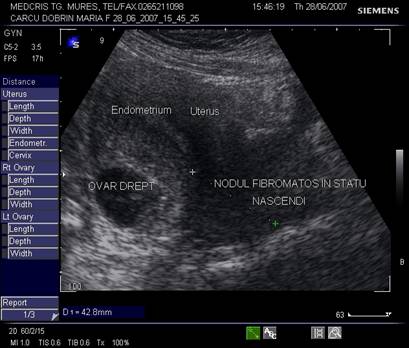

Fibromul uterin - cea mai frecvent intalnita tumora genitala, cu frecventa de 20 - 50% din femei [3].

Aproximativ 90% din fibroame (leiomioame) apar la nivelul corpului uterin. Se descriu, faza miomatozei difuze, fibroame intramurale, subseroase, submucoase, intraligamentare.Mioamele prezinta margini bine delimitate fata de miometru la ecografie, continand arii de mai mare sau mai mica ecogenitate in functie de modificarile degenerative.[1,6]

Fig. nr. 381.Nodul fibromatos ce prolabeaza prin canalul cervical, la ecografia abdominala